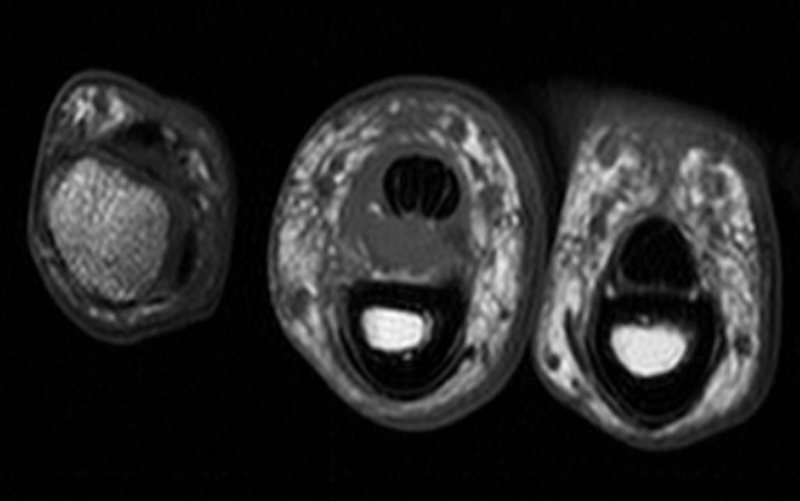

An A2 pulley tear in a 6yearold boy presenting with a history of mass... Download Scientific Torn A2 Pulley  Pain on the palm side of finger and tenderness with pressure.   an injury to the a2 pulley could be as simple as a mild strain, or as advanced as a complete rupture of the pulley.  how do you diagnose and classify pull the injuries?   the most common signs of finger pulley injuries include: Accurate diagnosis is necessary. Torn A2 Pulley.

A2 pulley injury ring finger Image Torn A2 Pulley  Measuring the distance of bowstringing of the flexor tendons from the bone using ultrasound. Hearing a pop at the time of the injury.   an injury to the a2 pulley could be as simple as a mild strain, or as advanced as a complete rupture of the pulley. A4 is the most flexible.   the most common signs of finger. Torn A2 Pulley.

Ultrasound image of the A2 pulley. Download Scientific Diagram Torn A2 Pulley  A4 is the most flexible. Most commonly, either the middle or index digit is the injured finger. A4 rupture often seen with a3 rupture.   the most common signs of finger pulley injuries include:  the most common injury in climbers is the a2 pulley sprain or rupture and is caused by overloading the tissue. Accurate diagnosis is necessary to. Torn A2 Pulley.

Ultrasound image of the A2 pulley. Download Scientific Diagram Torn A2 Pulley  Accurate diagnosis is necessary to identify.   the most common signs of finger pulley injuries include: Pain on the palm side of finger and tenderness with pressure. Hearing a pop at the time of the injury.   an injury to the a2 pulley could be as simple as a mild strain, or as advanced as a complete rupture of the. Torn A2 Pulley.